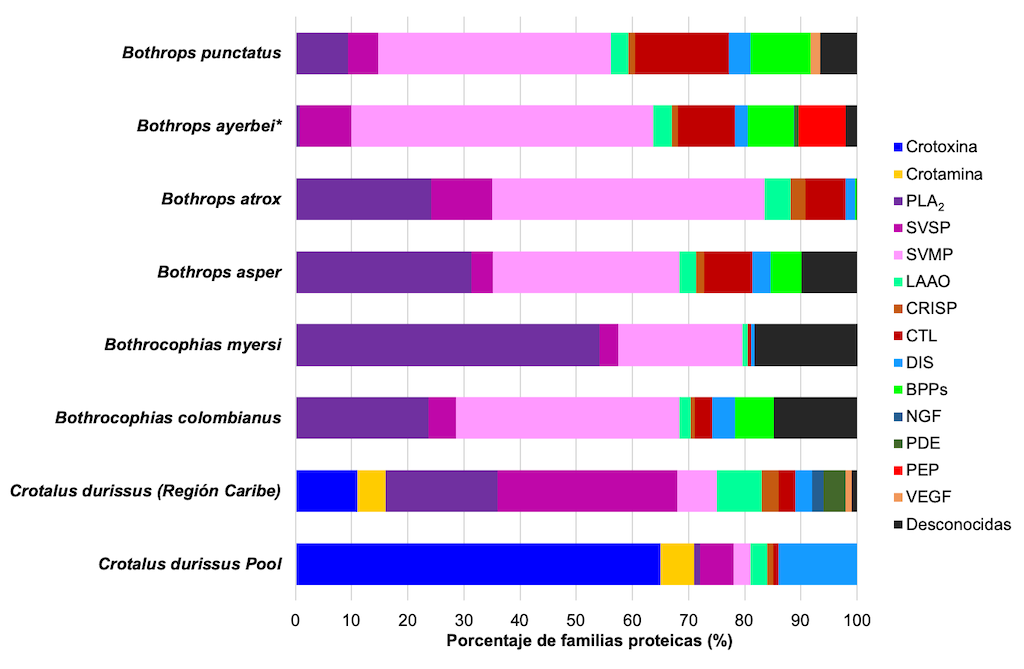

La variabilidad del veneno se produce debido a las trayectorias evolutivas de las serpientes venenosas, así como a la especialización de algunas de sus toxinas. Por ejemplo, los venenos tanto de las familias Elapidae y Viperidae están dominados por dos o tres familias de proteínas: fosfolipasas A2 (PLA2) y toxina de tres dedos (3FTx) para los elápidos, y metaloproteasas (SVMP), PLA2 y serino proteasas (SVSP) para los vipéridos. En promedio, estas familias de proteínas constituyen el 83% y el 67% del proteoma del veneno de elápidos y víboras, respectivamente [24].

Los venenos de serpientes de la familia Elapidae son principalmente neurotóxicos, mientras que los de la familia Viperidae inducen coagulopatías, hemorragias y daños tisulares locales [25,26]. Esto se debe a la prevalencia de las proteínas 3FTx y PLA2 en el veneno de elápidos que pueden causar debilidad similar a la miastenia gravis [27]. Esta debilidad puede afectar a cualquier músculo; y si el bloqueo neuromuscular afecta a los músculos de la respiración, puede provocar la muerte [26,27]. Por otro lado, el veneno de vipéridos tiene efectos principalmente hemotóxicos y miotóxicos. Los agentes identificados en el veneno de las víboras incluyen proteinasas similares a la trombina que provocan coagulopatía [28], hialuronidasas que alteran las matrices extracelulares, fosfolipasas A2 que causan inflamación local y dolor [29], y metaloproteasas que contribuyen a la hemorragia [30,31]. El resultado es una destrucción local del tejido empeorada por el efecto coagulopático [26].

Existe una amplia variación en los perfiles de veneno entre especies dentro del mismo género [32–34]. Por ejemplo, los perfiles proteómicos de los venenos de dos especies de vipéridos del género Bothriechis, B. lateralis y B. schlegelli, muestran que los venenos de estas dos especies contienen péptidos potenciadores de bradicinina (BPP) y proteínas PLA2, serinoproteasas, L-aminoácido oxidasas (LAAO), proteínas secretoras ricas en cisteína (CRISP) y metaloproteasas dependientes de Zn2+ (SVMP). Sin embargo, cada especie tiene una abundancia relativa diferente de cada familia de proteínas. Además, cada veneno contiene componentes distintos. Por ejemplo, B. lateralis contiene factor de crecimiento endotelial vascular (VEGF) y moléculas similares a lectina de tipo C, mientras que B. schlegelii tiene inhibidores de proteasa de tipo Kasal [35].

Las proteínas del veneno de ambas especies de Bothriechis son similares en menos del 10%, lo que indica una divergencia significativa en la composición del veneno. A pesar de que ambas especies se adaptan a hábitos arbóreos, las características bioquímicas de su veneno probablemente estén relacionadas con las características de las presas que consumen [32,35]. La composición de los venenos puede proporcionar pistas para racionalizar los diversos signos de envenenamiento causados por B. schlegelii y B. lateralis [35].

También existe variación en el perfil del veneno de serpiente entre individuos de la misma especie, encontrándose diferencias intraespecíficas por ubicación geográfica [28,36,37]. Por ejemplo, se analizó a nivel de subespecie la composición y el perfil toxicológico del veneno de la serpiente cascabel Crotalus simus en México. Los venenos de la subespecie C. s. simus, C. s. culminatus y C. s. tzabcan difieren en la expresión del complejo neurotóxico «crotoxina». Crotalus s. simus tiene la mayor concentración de crotoxina seguida de C. s. tzabcan, mientras que el veneno de C. s. culminatus está casi desprovisto de este PLA2 neurotóxico. El análisis proteómico se correlaciona estrechamente con los perfiles toxicológicos. Por ejemplo, C. s. simus contiene altas cantidades de crotoxina y serinoproteasas, mientras que el veneno C. s. culminatus tiene mayores cantidades de metaloproteasas y crotamina. Esto sugiere que la variación geográfica en la composición del veneno puede reflejar la selección natural para alimentarse de presas locales [38]. La creciente aparición de crotamina en poblaciones de Crotalus es razón suficiente para advertir sobre la necesidad de desarrollar un antiofídico que pueda neutralizar esta toxina [36].